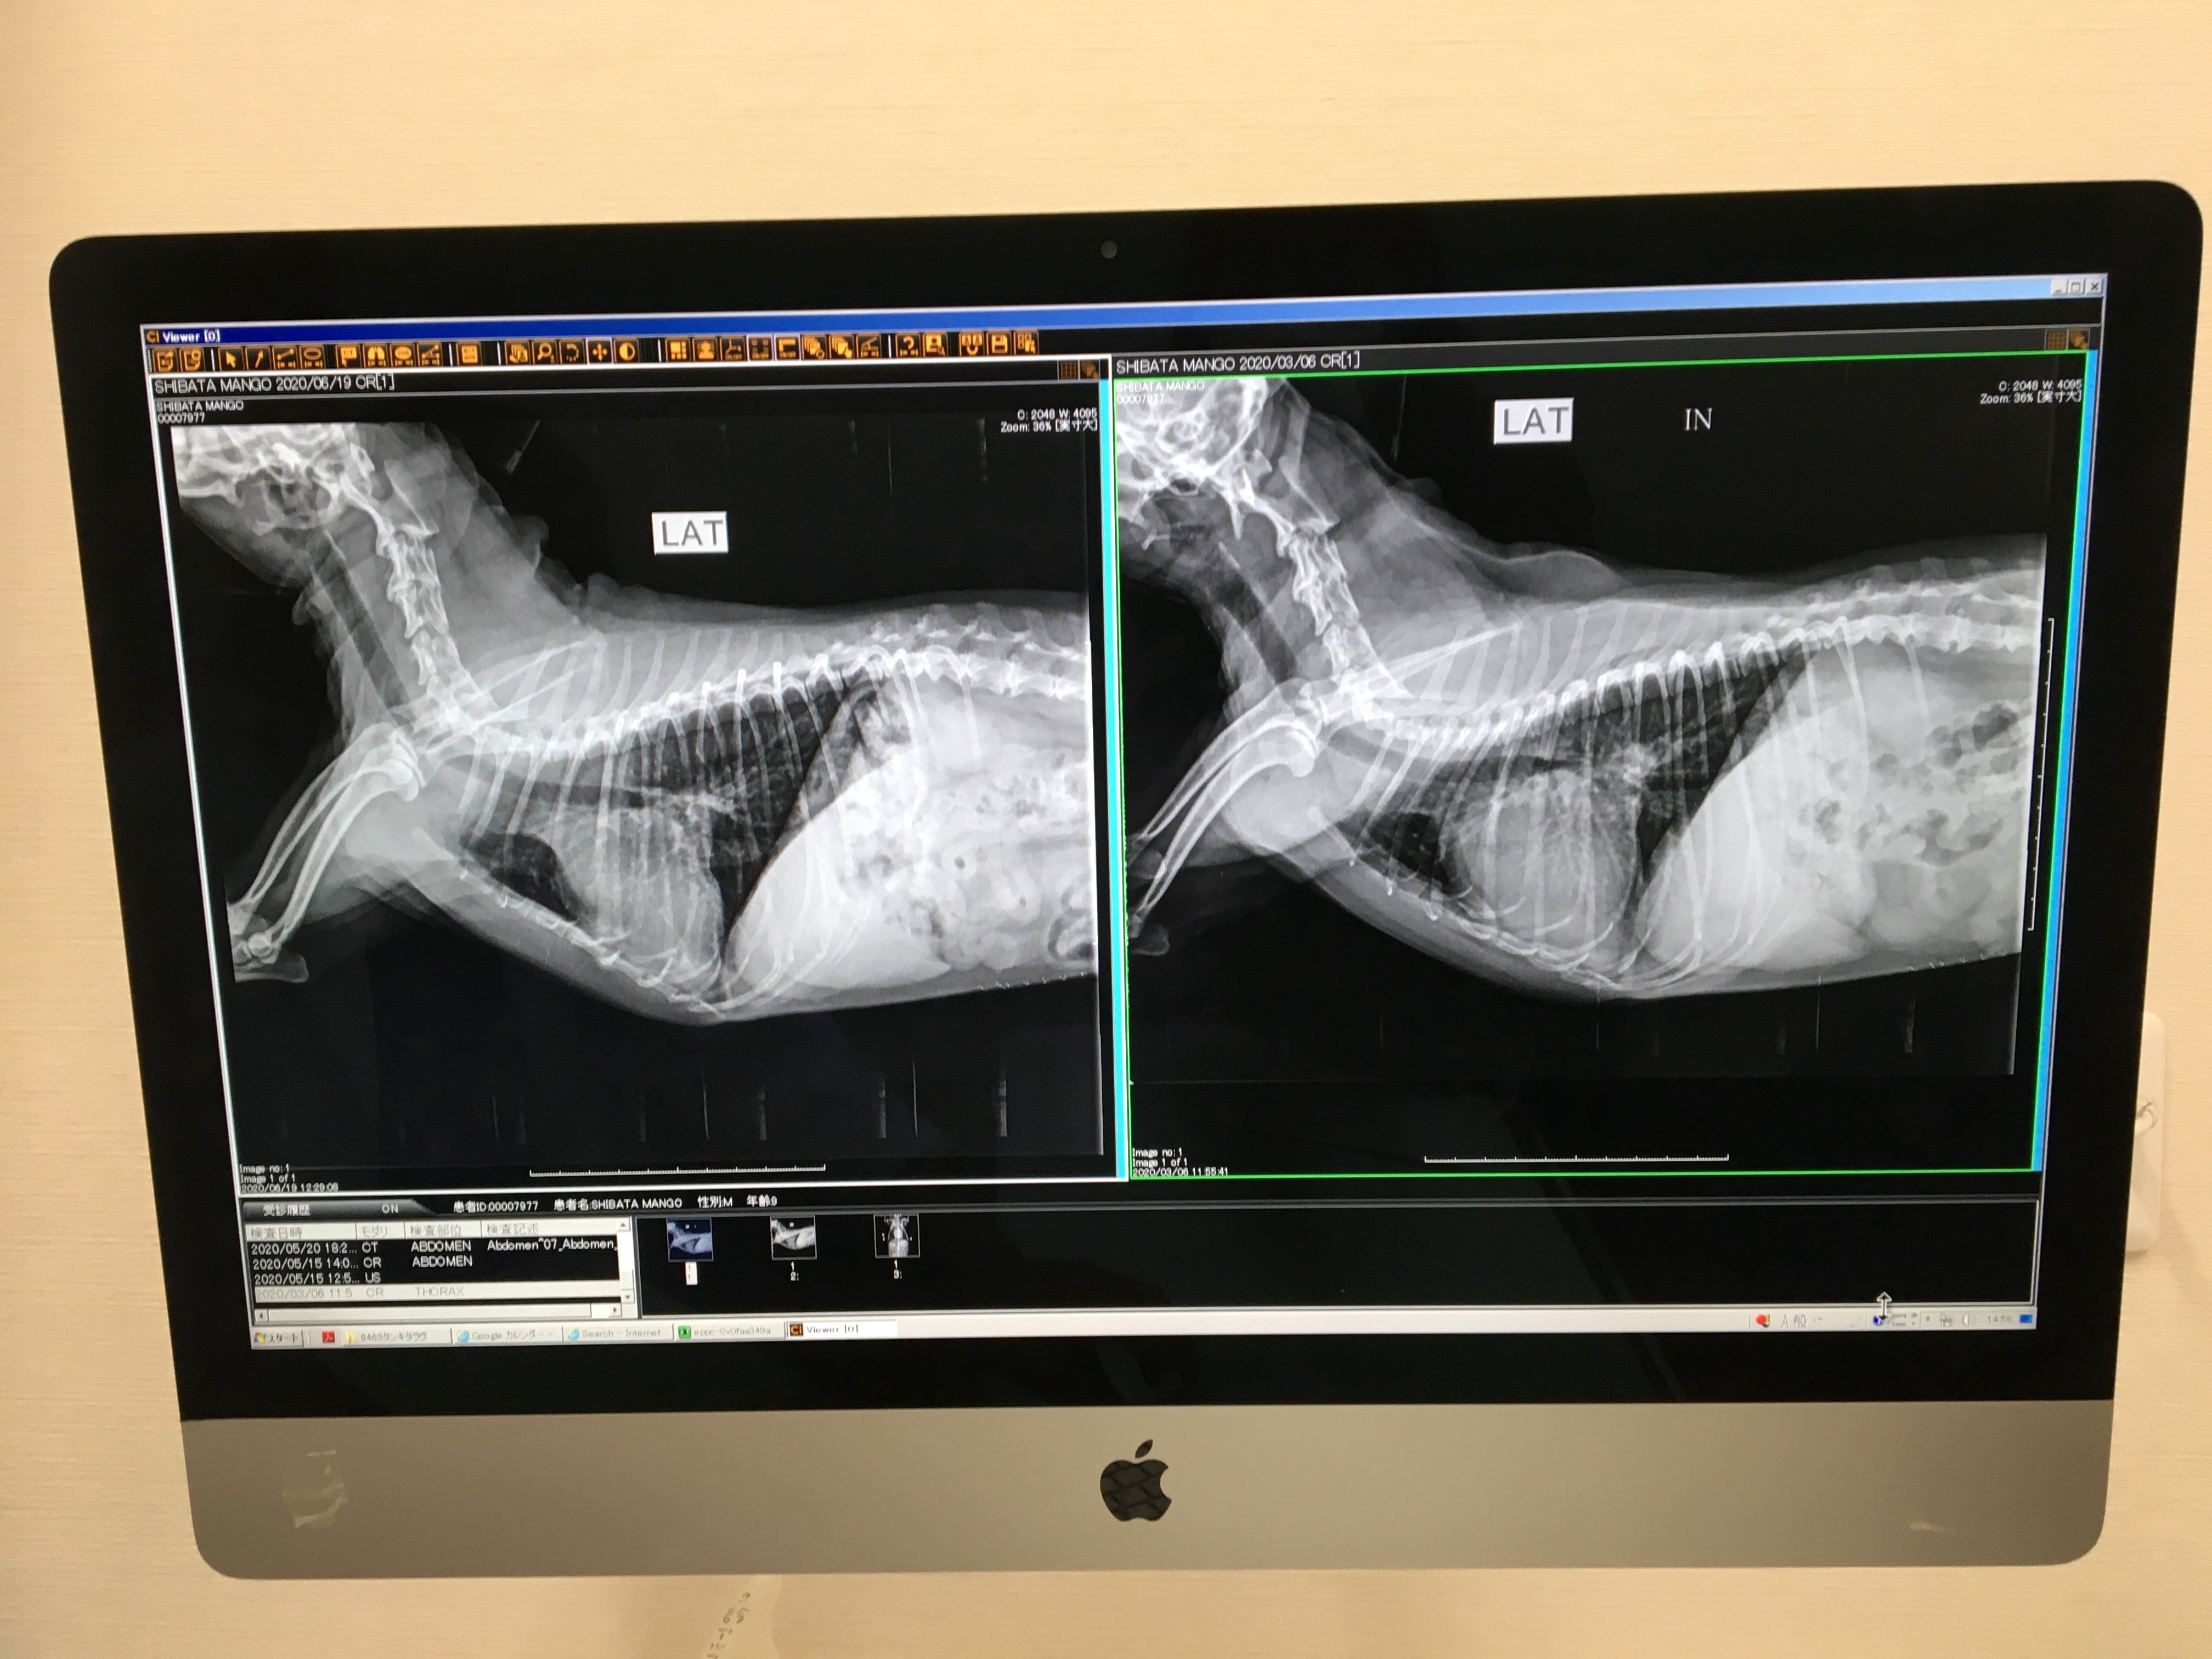

左が術後、右が術前です。

心臓がすごく小さくなっています。